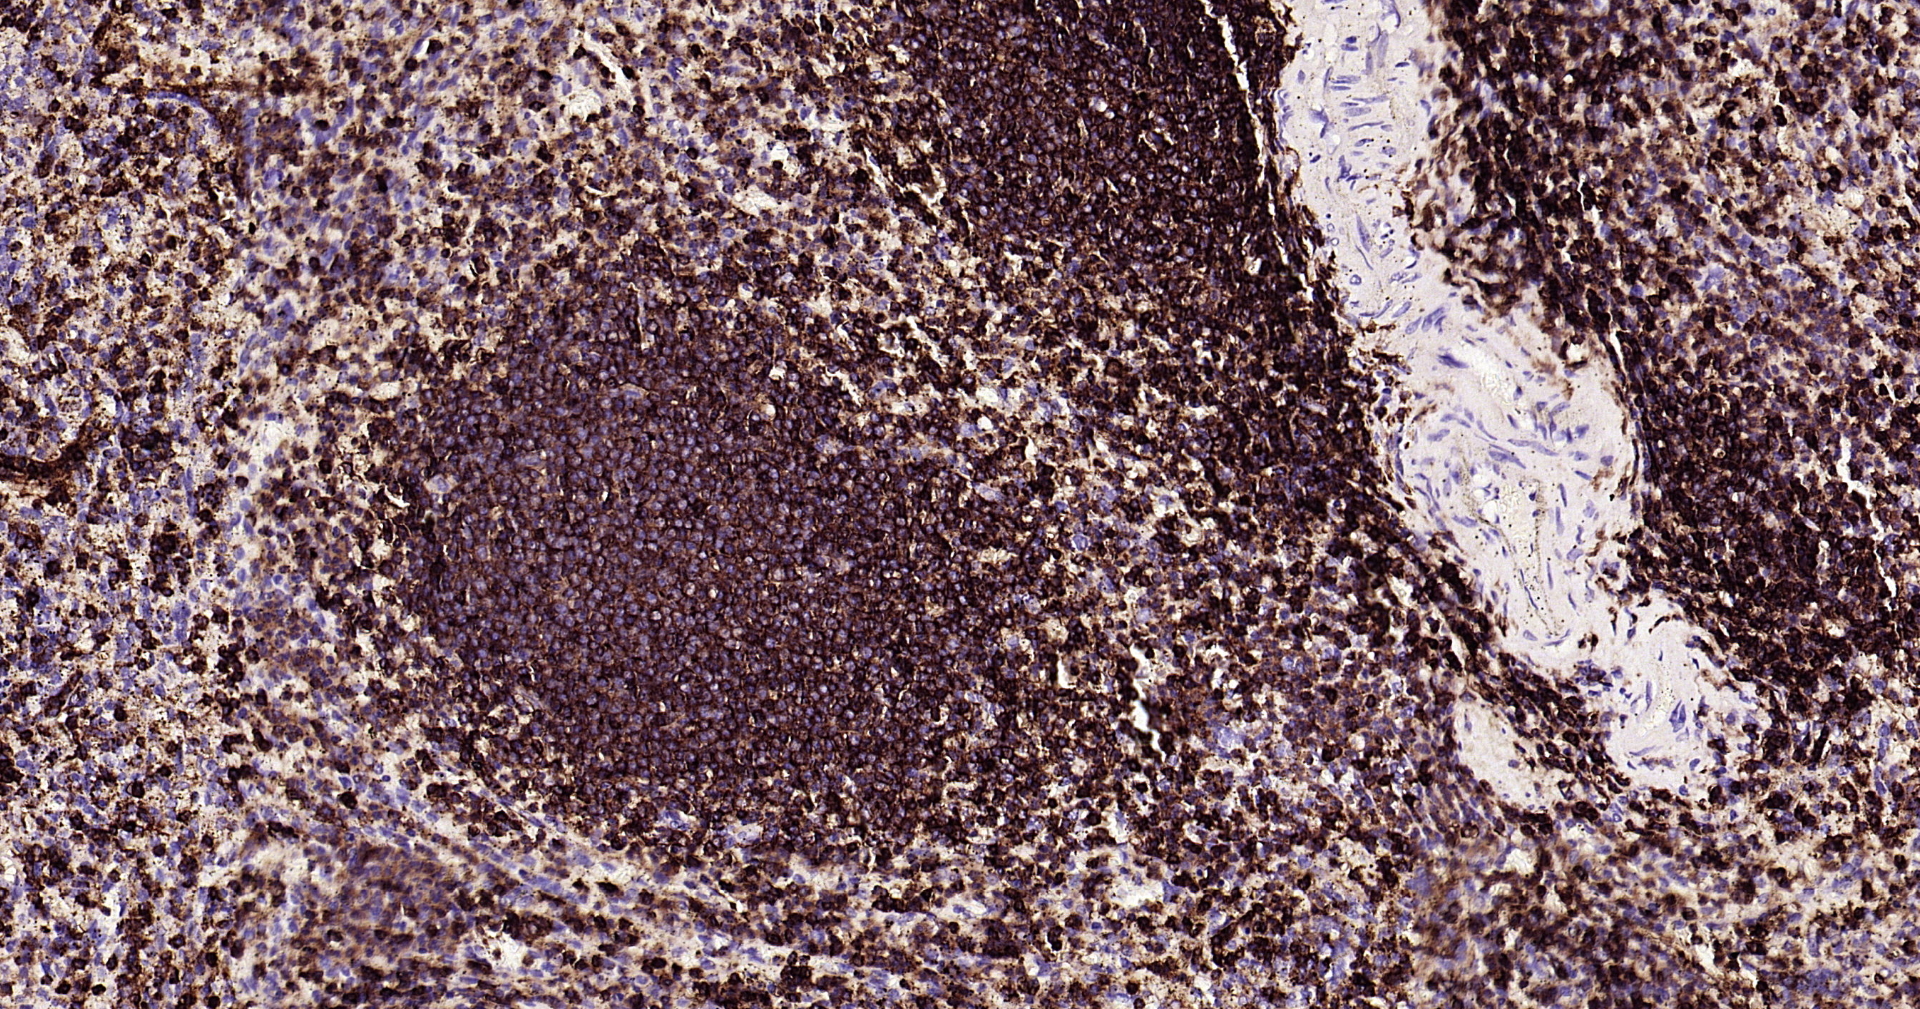

CD45 Recombinant Antibody

• IHC-P

IHC-P IHC-P1:100-500